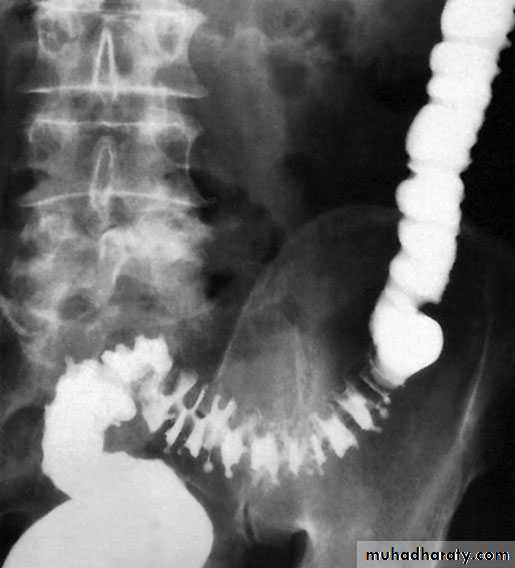

Barium enemas and sigmoidoscopy are usuallyreserved for patients who have recovered from an attack of acute diverticulitis, for fear of causing perforation or peritonitis. Watersoluble contrast enemas may, however, be helpful in sorting out patients with large bowel obstruction. In the acute situation, it is good at detecting intraluminal changes and leakage. The sensitivity for this is of the order of 90%. Barium radiology is carried out to exclude a carcinoma and to assess the extent of the disease.

Where the sigmoid colon is thickened and narrowed, a ‘sawtooth’ appearance may be seen. Some strictures can be very difficult to distinguish by radiology alone and, in those circumstances, colonoscopy will be necessary to rule out a carcinoma. Vesicocolic fistulae should be evaluated with cystoscopy and biopsy in addition to colonoscopy. Contrast examinations may show the fistula itself. The differential diagnosis for vesicocolic fistulae (and other fistulae) includes cancer, radiation damage, Crohn’s disease (CD), tuberculosis and actinomycosis.